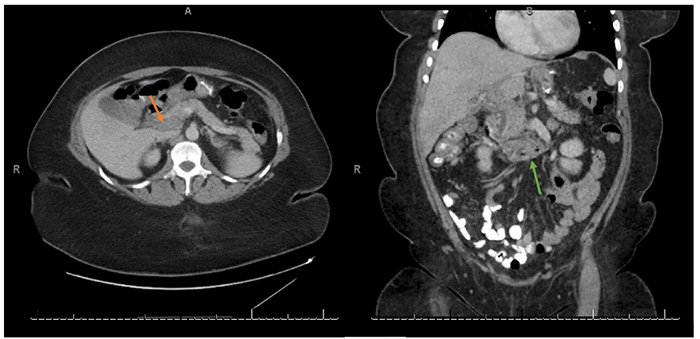

A 46-year-old morbidly obese African American woman presented with abdominal pain 13 days postlaparoscopic sleeve gastrectomy. Her pain was central and sharp in quality. She denied nausea, vomiting, or change in bowel habits. She also denied fever, chills, or dysuria. She was afebrile, hemodynamically stable, and her body mass index was 42.92. She had diffuse tenderness to deep palpation but did not exhibit peritoneal signs on exam. Labs were pertinent for mild leukocytosis, but electrolytes, blood urea nitrogen, and creatinine were within normal limits. Computed tomography (CT) of the abdomen and pelvis (Figure 1 and Figure 2) were suggestive of extensive portal vein thrombosis (PVT) that was confirmed with a follow-up ultrasound doppler study showing no flow in both branches as well as in the main portal vein (Figure 3 and Figure 4).

Figure 1. Axial CT abdomen/pelvis with oral and intravenous contrast showing opacification of the hepatic artery (red arrow) and unopacification and distension of the main portal vein (blue arrow), suggestive of an acute thrombus.

Figure 2. Axial and Coronal CT abdomen/pelvis with oral & intravenous contrast showing hypoattenuation of the main portal vein (orange arrow), intrahepatic portal veins, and involvement of the superior mesenteric vein (green arrow).